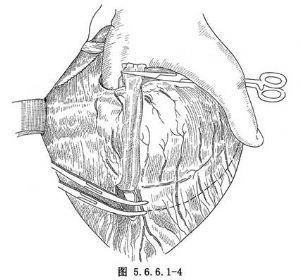

(3)游离胃:探查腹腔,如腹内无明显转移,在胃体上2/3与1/3交界处的小弯侧将胃肝韧带切开,再由相对应的胃大弯侧切开胃结肠韧带,用一条纱带越过胃后将胃向上牵引(图5.6.6.1-4)。继续切开胃结肠韧带,保留胃网膜右动脉,将韧带中的血管钳夹后切断结扎(图5.6.6.1-5)。切开胃脾韧带,切断结扎胃短动脉分支。在暴露术野时注意牵拉脾脏不能用力过大,以免撕裂脾脏(图5.6.6.1-6)。胃大弯侧游离足够以后,离断胃肝韧带,保留胃右动脉(图5.6.6.1-7)。在贲门下方附近的小弯侧摸到搏动的胃左动脉,用3把止血钳夹住,近侧两把,远侧1把,切断后先缝扎一道,再由其深部结扎一道(图5.6.6.1-8),缝扎胃侧血管断端。如此时胃左动脉近侧残端有出血,应先用指压住出血点,再请第一助手以拇指用力按压胸主动脉即可止血,用吸引器将积血迅速清除后,即可从容寻找到出血处予以处理。小弯侧游离完后,在离断贲门之前,请麻醉师将胃管连接在吸引器上持续吸引,将胃内容物尽量吸净,如此可以减少污染并方便吻合操作,吸引完后将胃管向外拔,使其尖端置于贲门上方3~4cm处。用大号直止血钳夹住贲门切断(图5.6.6.1-9)。胃侧断端用中号丝线贯穿缝合,再将浆肌层对拢间断缝合。食管侧断端用贯穿缝合封闭后用阴茎套保护之。将游离完毕的胃提至胸腔。